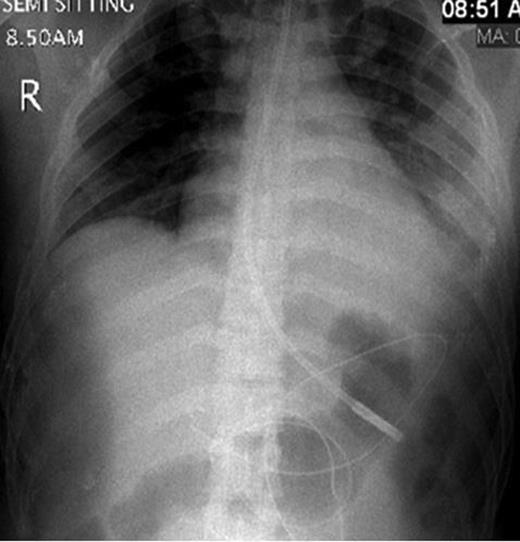

CT abdomen showing two hepatic lacerations in addition to minimal subhepatic and left subdiaphragmatic free fluid.

Definite management of pancreatic injuries is not well defined yet. Moreover, the clinical and laboratory findings of blunt pancreatic injury are nonspecific, and therefore accurate diagnosis in its acute phase is usually delayed [1, 3]. Computed tomography scanning may fail to delineate the pathology, especially in the initial stage. Also, the ability for CT to demonstrate the integrity of pancreatic duct is limited (43%); however, multiple detector computed tomography may have better result [1, 4, 5].